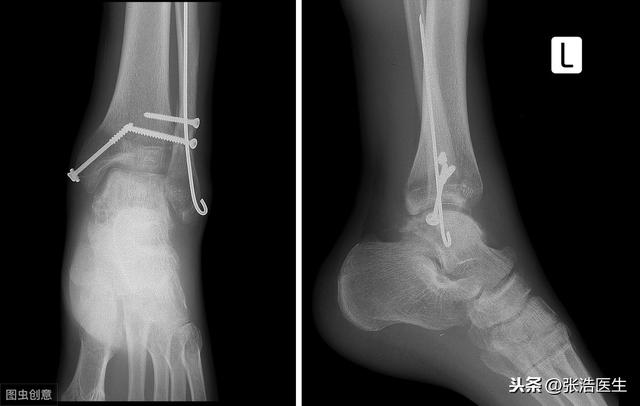

脚的组成包括胫腓骨下端与距骨。踝关节因为其要承受身体大部分的重量,所以其抗压性是较高的,但是其稳定性不足,所以就导致踝关节最容易出现内翻、外翻,也就是我们说的崴脚,损伤的主要是两侧的韧带。

踝关节骨折后最明显的特征就是关节局部的疼痛、肿胀,这些表现实际上单纯的软组织损伤也会出现。所以就很容易错把骨折当成一般的软组织损伤。普通的软组织损伤一般经过一两周的休息后,肿胀疼痛都会消失,而骨折导致的疼痛,并不会消失,甚至会加重,尤其是在运动的时候。

所以说,单纯的凭借能不能运动时无法判断有没有骨折的,如果明显肿胀,为了健康着想,建议还是去医院做个x线的检查,这个做起来也方便,不需要提前很久预约,价格也比ct、核磁便宜很多。另外对于习惯性崴脚的人,可以再进行一下踝关节韧带的检查,防止再次发生崴脚。#清风计划##关注精神健康##生命召集令超能团#@清风计划@生命召集令@健康真相官